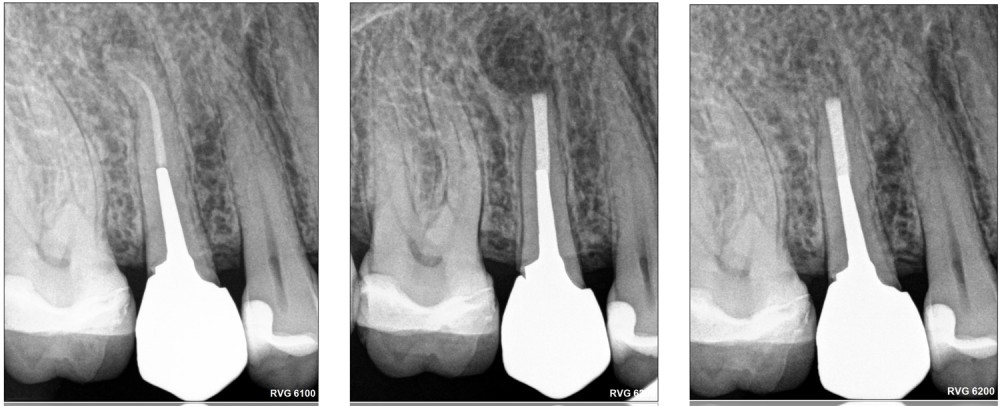

La chirurgie endodontique ne se limite pas à couper la racine mais consiste en un traitement endodontiquea retro. Comme pour le retraitement par voie orthograde, l’intervention peut intéresser un ou plusieurs canaux. L’imagerie est l’élément clé de la décision. Le CBCT (Cone Beam Computed Tomography) vient au service du sens clinique du praticien.